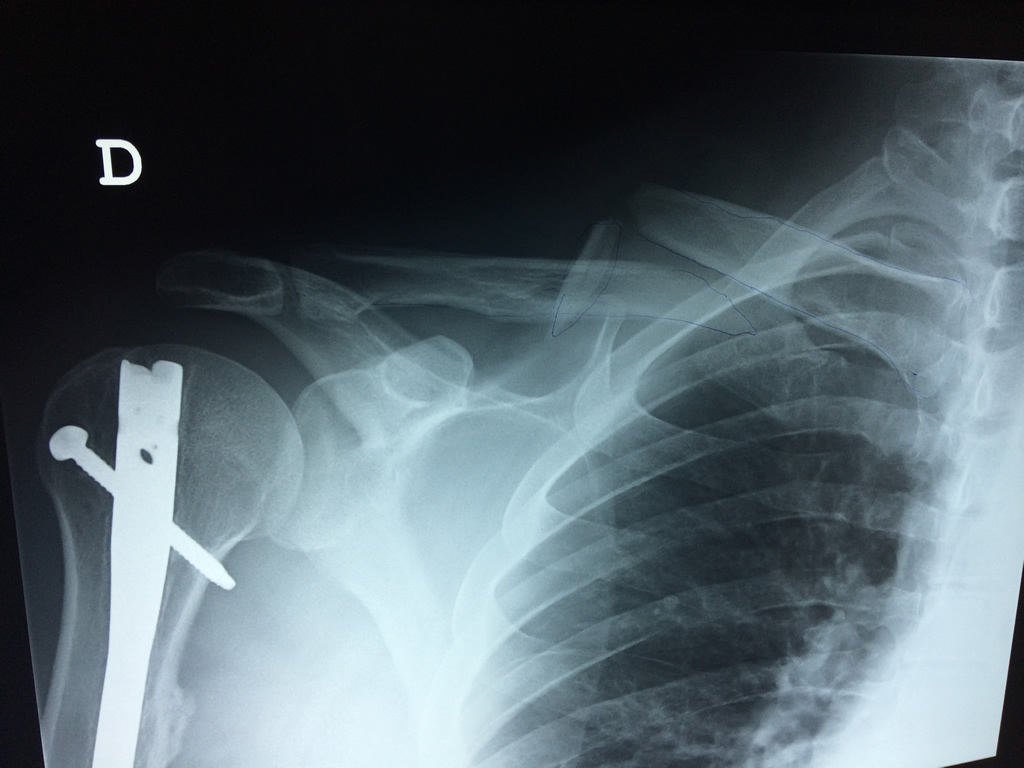

Clavicula 2

Detail Download